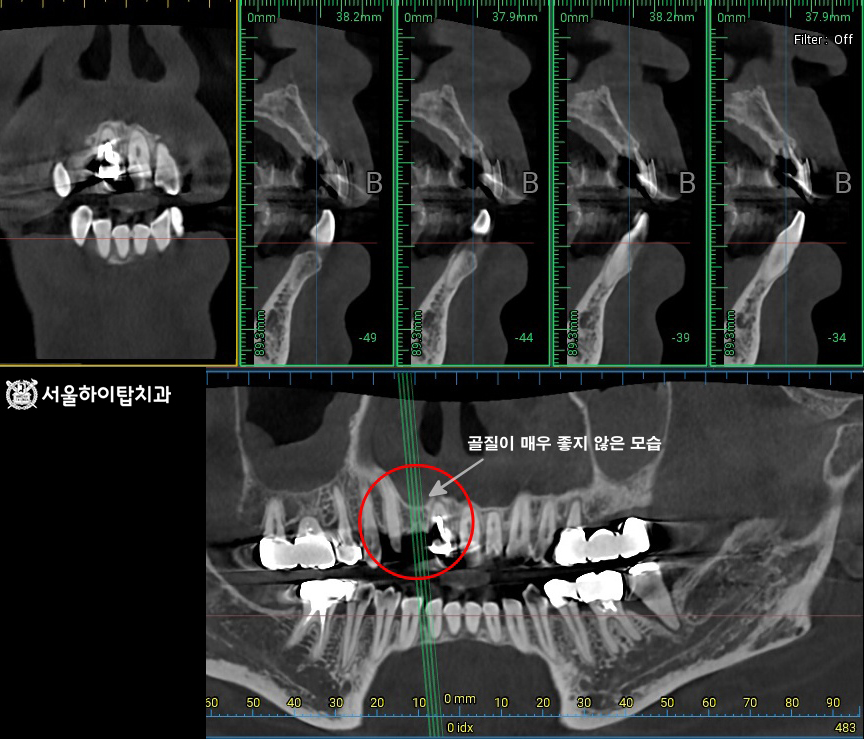

초진 파노라마 엑스레이입니다.

십정동 치과 에서 표시해 둔 부위를 보면

상실된 앞니를 확인할 수 있습니다.

치아가 상실되면 인접치와 치조골에서는 위치 변동과 골 흡수가 나타날 수 있는데,

다행히 해당 X-ray에서는 눈에 띄는 변화는 없는 것으로 보입니다.

다만, 주변 골질이 다소 좋지 못한 모습은 확인되며,

이는 뼈의 밝기와 내부 패턴을 통해 간접적으로 판단할 수 있습니다.

정상 치조골은 비교적 선명하고 균일한 밝기를 보이지만,

골밀도가 낮아지면 해면골 패턴이 성글게 보이거나

피질골의 윤곽이 흐릿하게 나타나는 특징을 보입니다.

쉽게 말씀드리면, 단단한 뼈처럼 하얗게 보이지 않고

상대적으로 검게 비어 보이는 경향이 있다고 이해하시면 됩니다.

계획 수립 및 CBCT 촬영

이에 따라 임플란트가 결정되었다면,

십정동 치과 에서는 정밀한 CT 촬영을 통해

임플란트가 식립될 위치를 정확히 확인하게 된다고 설명드립니다.

이 과정에서 뼈의 높이, 밀도, 두께 등을 면밀히 분석하며,

다소 좋지 않아 보였던 골질도 CT를 통해 더욱 뚜렷하게 확인할 수 있습니다.

이러한 경우에는 치조골 이식(골이식)을 함께 고려하게 되는데,

골질이 좋지 못하다는 것은 뼈가 단단하지 않고 치유 능력이 떨어져

식립 후 초기 고정력이 충분히 확보되지 않을 가능성이 있기 때문입니다.